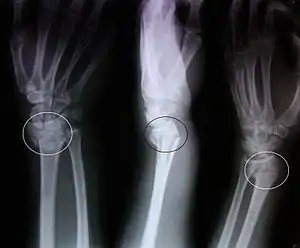

| پرتونگاری شکستگی کالیس با جابجایی کم و دفرمیته واضح | |

پرتونگاری با اشعه ایکس از نماهای قدامی_خلفی و جانبی روش اصلی تشخیصی میباشد . شکستگی کلاسیک استخوان کالیس (colles) دارای مشخصات زیر است: -شکستگی عرضی استخوان زند زبرین (رادیوس) -شکستگی در یک اینچی نزدیک به مفصل رادیو کارپال -جابجایی غیر طبیعی مچ دست به سمت پشت و ایجاد زاویه پشتی غیر عادی.